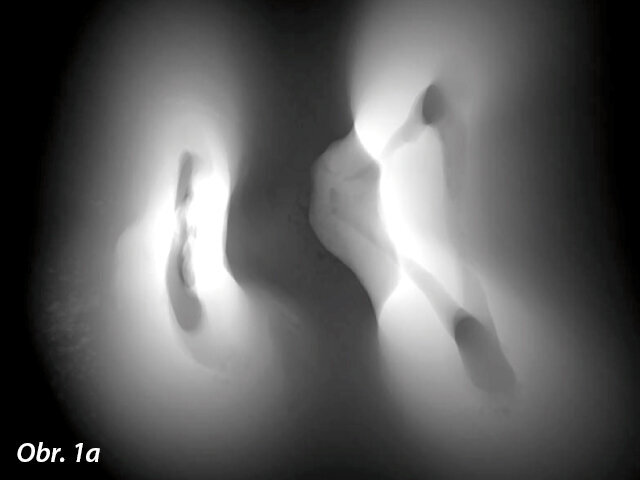

V tehdejších dobách se jednalo o radikální inovace a navzdory technologickým a biologickým nedostatkům dostupných nástrojů, které byly k dispozici, měly být tyto inovace technologicky realizovány a měly být odstraněny nedostatky ve vývoji materiálů a výrobních procesů; nicméně až donedávna se tak v podstatě nestalo. Abychom skutečně porozuměli vlastním nedostatkům, musí lékař poznat komplexnost toho, co je nezbytné k dosažení předvídatelného klinického úspěchu v endodoncii. Studie hodnotící průměrné rozměry apikální anatomie opakovaně prokázaly, že bukolingvální průměr je větší než meziodistální; kanálky jsou v převážné většině průběhu oválné, ne okrouhlé (obr. 1a, b).1-4

Tento axiální pohled na dolní molár demonstruje ovoidní excentricitu kanálků a existenci jistého spojení mezi meziobukálním a meziolingválním kanálkem v souladu s nálezy četných studií.